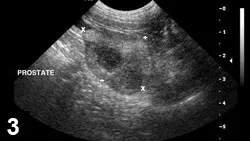

Featured Image

FIGURE 3

Prostatitis with abscess. Sagittal view of an intact canine prostate (cursors); a hypoechoic nodule is visible within the parenchyma. The parenchymal echo texture is mixed.

• Ultrasonographic findings are nonspecific but typically will be of mixed echotexture with hyperechoic areas reflecting fibrosis (Figure 3).